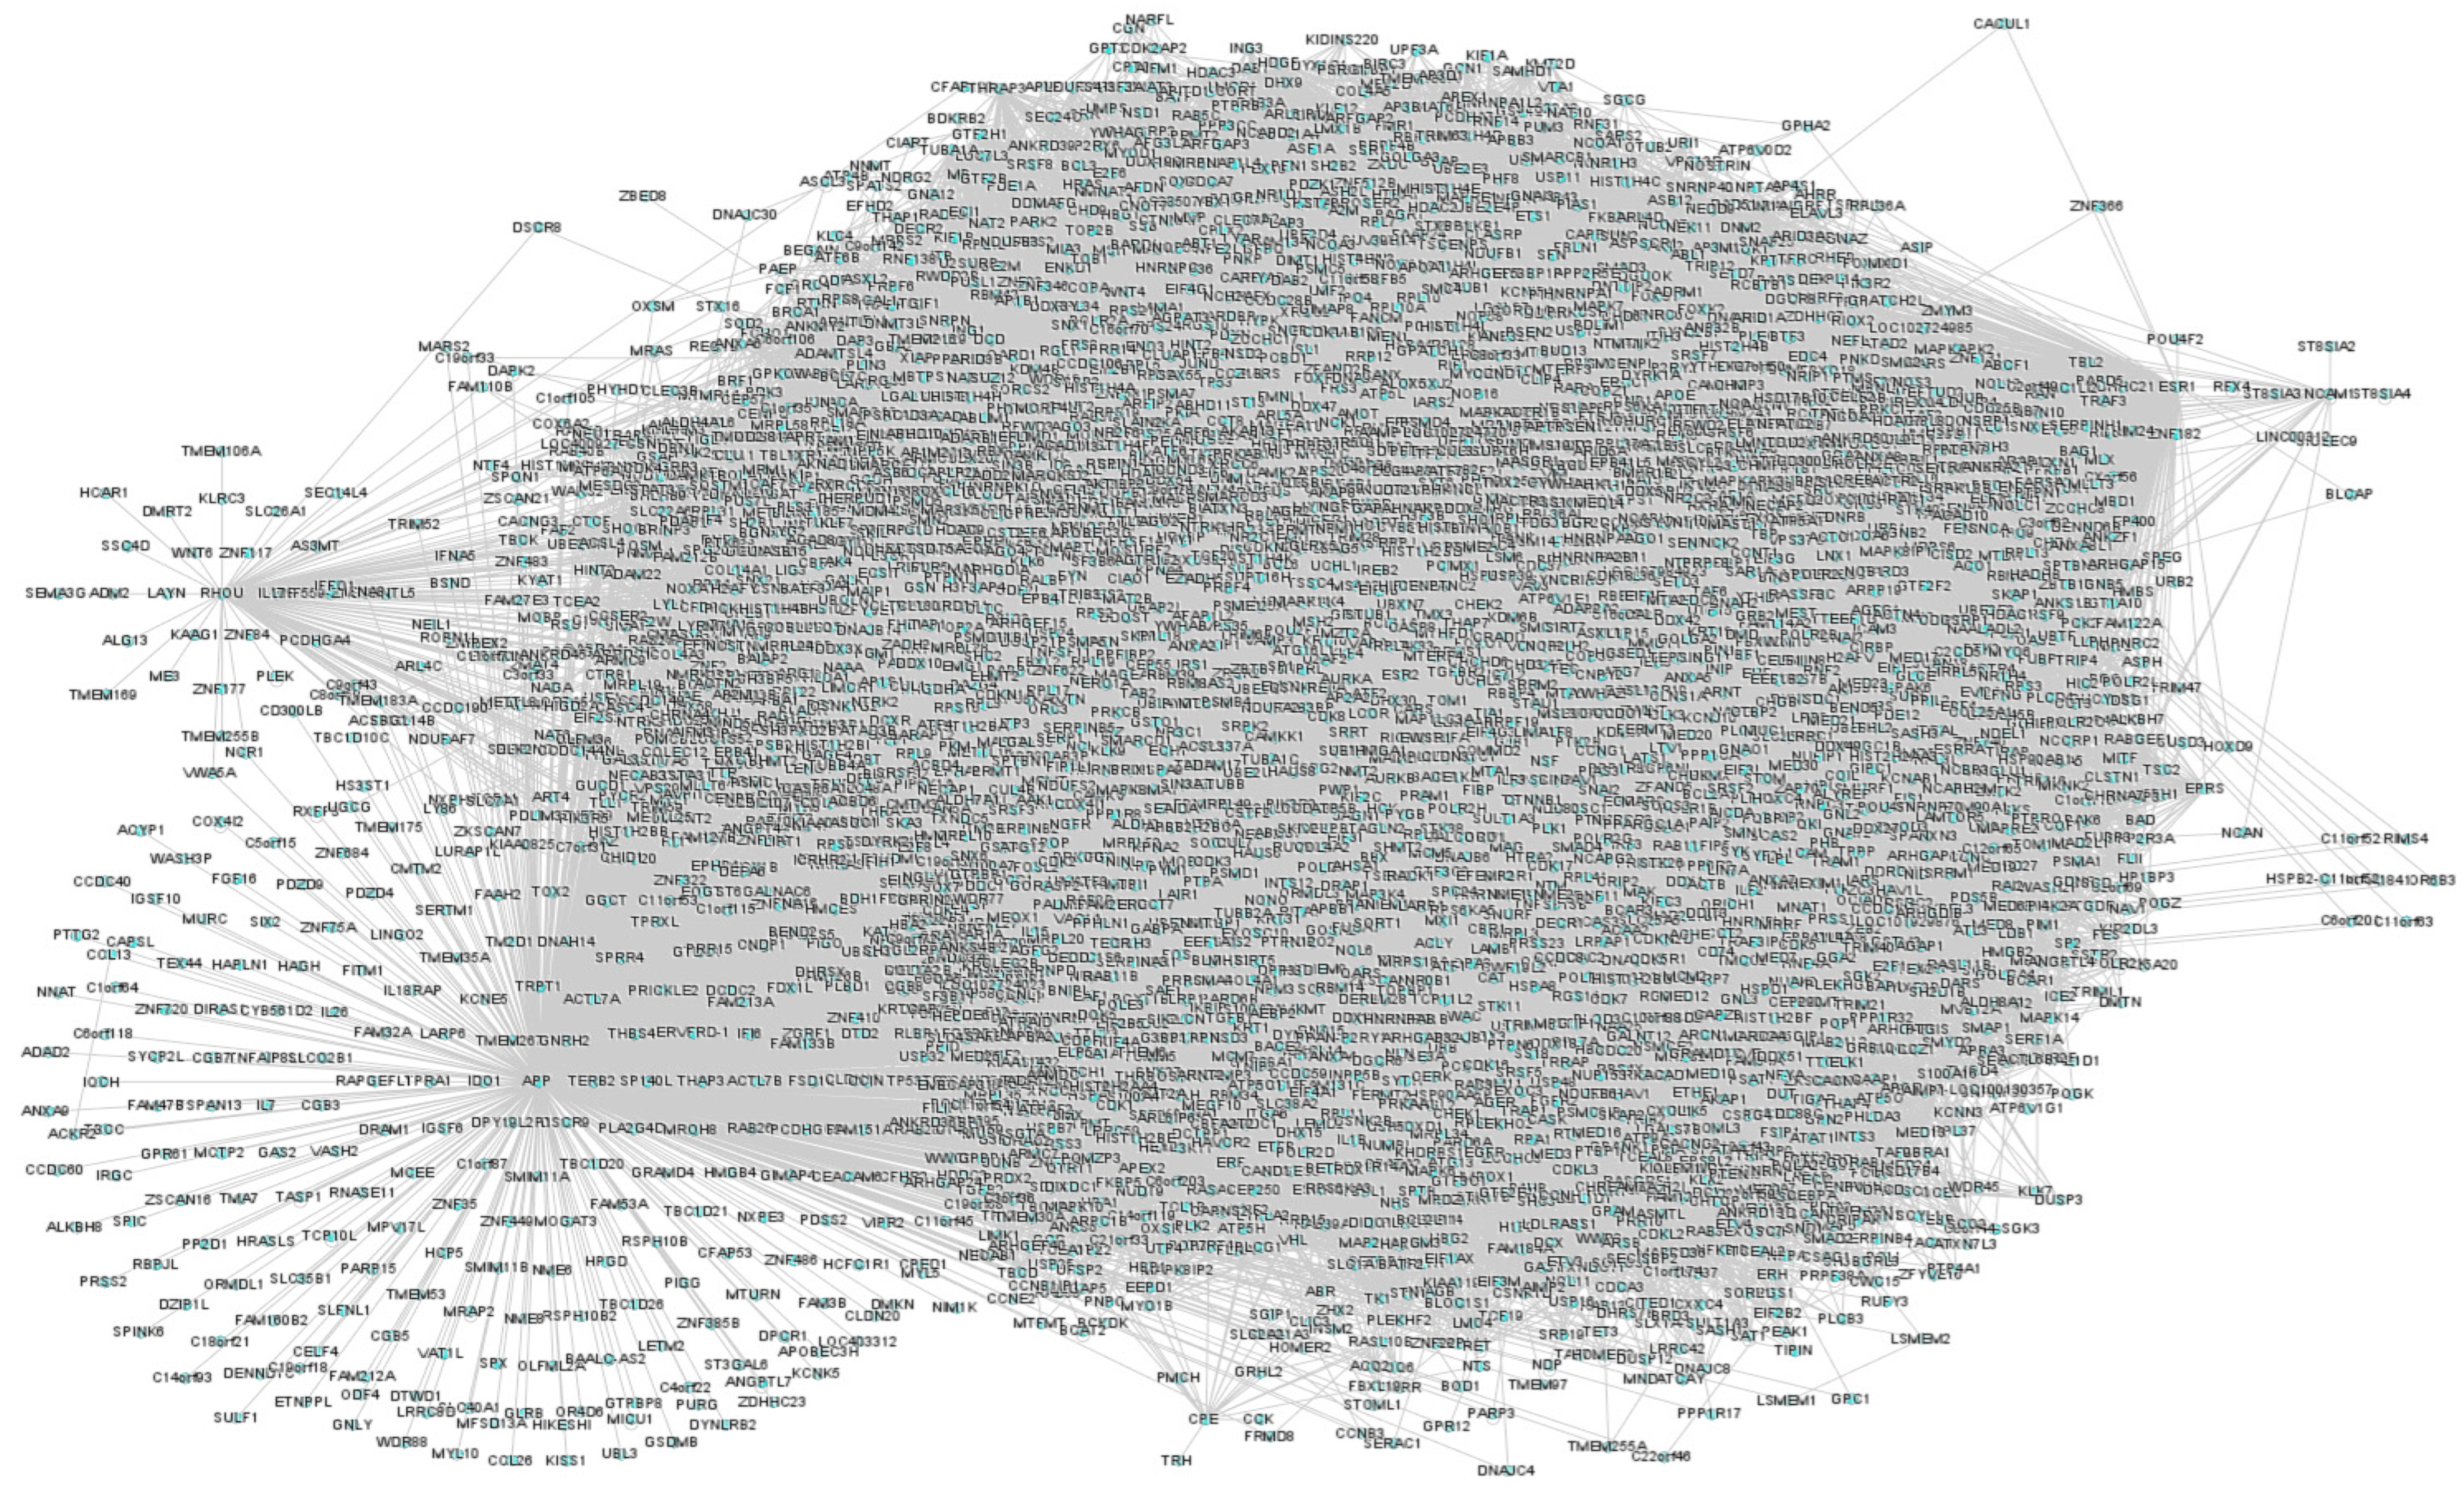

3.1. Text-Mining and T2DM Network